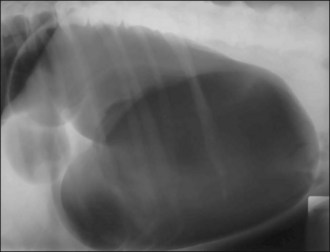

Aggressive intravenous fluid resuscitation with an isotonic crystalloid solution was commenced and morphine (0.3 mg/kg slow i.v.) administered. Abdominal ultrasound revealed the presence of enlarged uterine horns distended with hypoechoic fluid consistent with pyometra and peritoneal fluid was detected (Figure 29.1).

Figure 29.1 Ultrasound image of pyometra showing enlarged uterine horns distended with hypoechoic fluid; the urinary bladder is also visible.